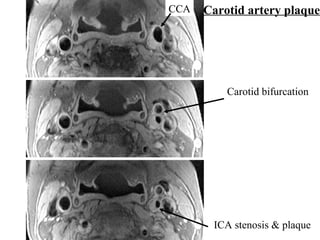

The document describes the Pathway MRITM Carotid Array coil, which is designed for high resolution imaging of small soft tissue structures like the carotid arteries. It provides images showing atherosclerotic plaque buildup in the carotid arteries, including plaque in the common carotid artery, carotid bifurcation, and internal carotid artery stenosis and plaque.